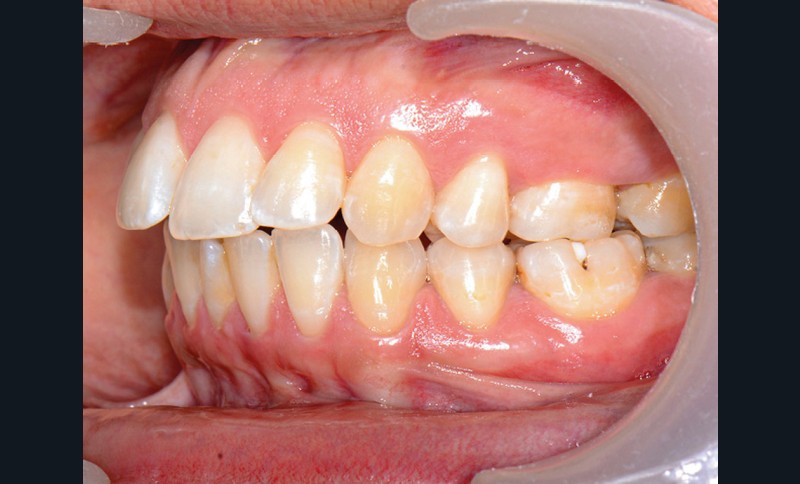

C’est précisément le cas de cette patiente de 33 ans qui présente une classe II squelettique par rétrognathie mandibulaire sur un schéma vertical hyperdivergent associée à une classe II/1 dentaire avec DDA par excès et biproalvéolie. Son profil est convexe, cis-frontal et, sur le plan fonctionnel, on peut observer une dysfonction linguale et une incompétence labiale au repos. Il en résulte une contracture des muscles de la sphère péri-orale lèvres jointes. La formule dentaire n’est pas complète puisque les quatre deuxièmes prémolaires ont été extraites lors d’un premier traitement orthodontique et qu’il y a également agénésie des troisièmes molaires 18 et 38 (fig 1 à 11).